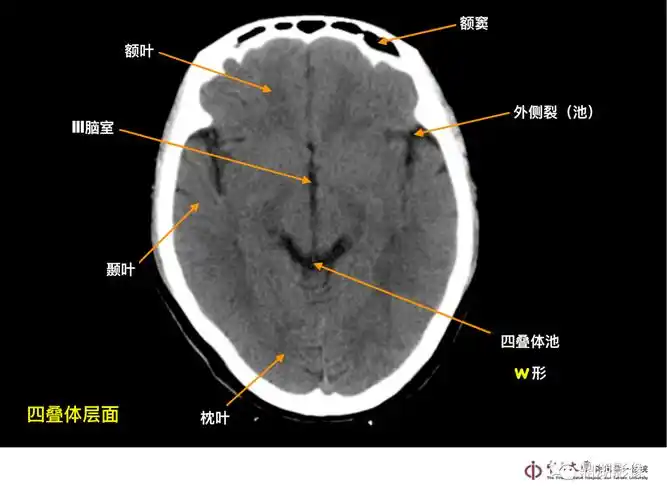

读懂头颅ct并不难教你成为读片小能手

头颅ct断层解剖

头颅ct解剖与常见出血梗死判读

详细标注版——颅脑ct正常解剖图谱_中央_小脑_纤维